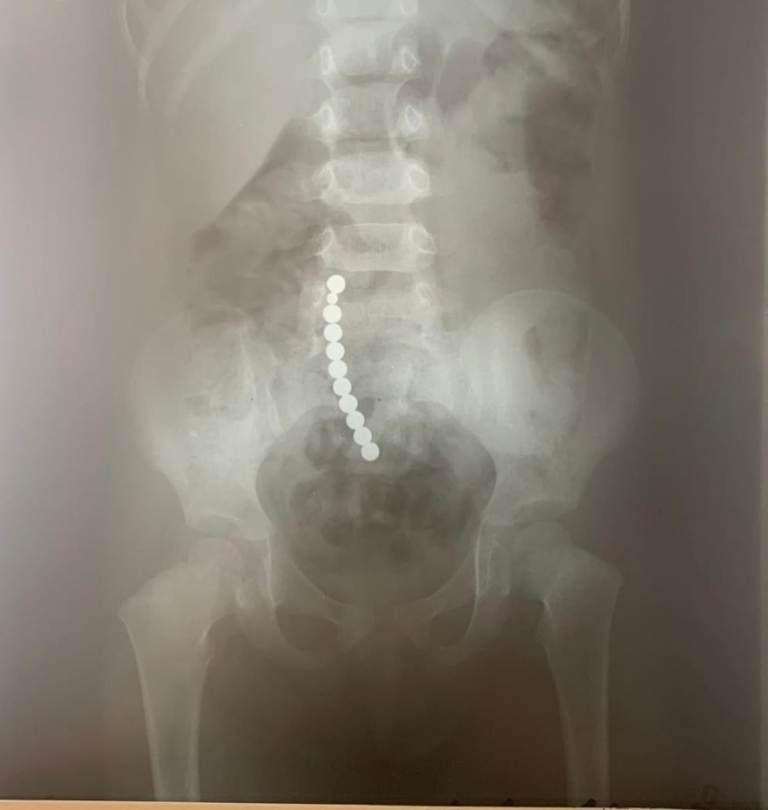

„Acești magneți sunt foarte puternici, iar ingestia lor poate duce la probleme gastrointestinale grave. Odată înghițiți sunt atrași unul spre altul chiar dacă se găsesc în secțiuni diferite ale tubului digestiv. O ansă intestinală prinsă între acești magneți se poate perfora ducând la tratament chirurgical de urgență. În secția noastră, de la începutul anului s-au prezentat trei cazuri, două fete și un băiat, cu vârste cuprinse între 2 și 4 ani.

Aceștia au suferit perforații la nivelul intestinului subțire și au necesitat intervenții pentru îndepartarea porțiunii de intestin afectate”, a precizat dr. Adriana Constantineanu.